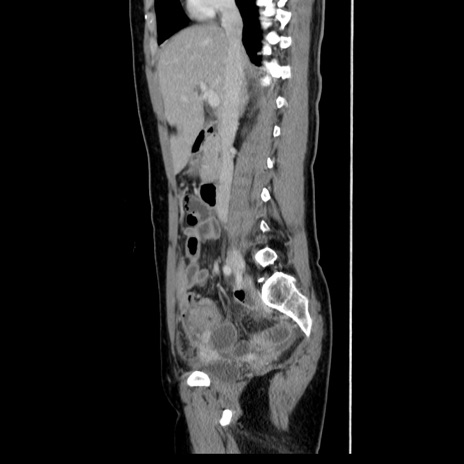

症例39(矢状断像)

【症例】40歳代女性

【主訴】上下腹部痛

【現病歴】2日目から下腹部痛あり。夜間は痛みで眠れなかった。昨日より上腹部痛と下痢が出現。臥位で痛みは軽快したため、休んでいた。本日になって臥位でも立位でも痛みが強くなってきたため救急要請。

【既往歴】子宮内膜症

【身体所見】部:平坦・軟、左上下腹部に圧痛あり、反跳痛あり。

【データ】WBC 21800、CRP 26.78

CT